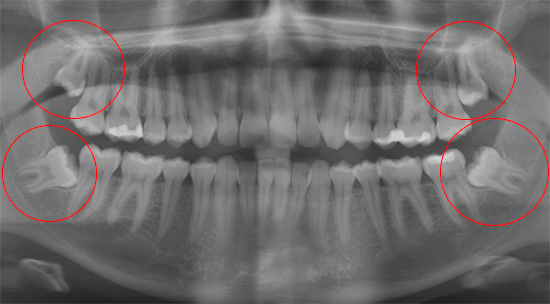

Qualsiasi dentizione difficile del dente del giudizio con dolore alla gengiva e ai tessuti circostanti richiede una diagnostica a raggi X. Per determinare la posizione del dente nella mascella (angolo di inclinazione, struttura, forma), viene utilizzato un ortopantomogramma (OPTG) o un'immagine panoramica di tutti i denti su entrambe le mascelle.

Puoi anche effettuare uno scatto mirato su un visiografo, un dispositivo che trasmette un'immagine al monitor di un computer. Dopo che il dentista sa con cosa ha a che fare, pianifica un'operazione: spiega i rischi per il paziente, il tempo approssimativo della procedura, le caratteristiche del periodo postoperatorio dopo la rimozione del dente del giudizio, ecc.

Spesso i denti inferiori della saggezza iniziano a tagliare e ferire, ma non hanno fretta di apparire sulla superficie delle gengive.Nelle immagini è possibile osservare come il dente "saggio" sia quasi in inclinazione orizzontale rispetto a quello adiacente, per cui in alcuni casi clinici inizia anche a provocare dolore. Anche nel dente del giudizio che non è ancora apparso sulla superficie delle gengive, possono verificarsi carie e sue complicazioni, poiché i batteri cariogeni passano facilmente sotto la gomma dietro il penultimo "sette".